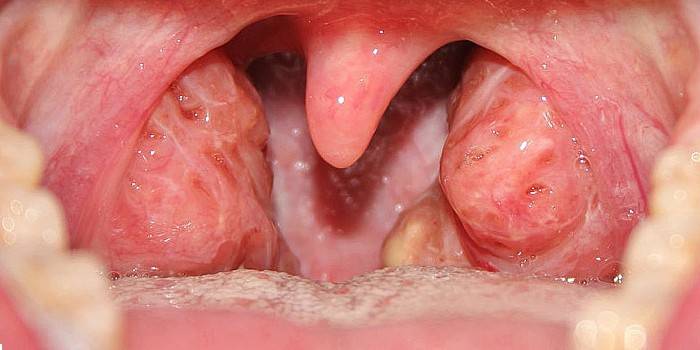

- Lacunar angina - na lazniach mandlí je viditeľný belavý povlak, ktorý sa môže šíriť okolo vredov. Je odstránený lekárom pomocou špeciálnych nástrojov.

- Folikulárna tonzilitída - ťažko zanedbaný katar. Vlasové mandle zväčšujú, zväčšujú sa, je cítiť silnú bolesť, nie je možné prehltnúť tuhé jedlo. Pacientka má horúčku, bolesť a zvýšenie lymfatických uzlín.

Fotografie hnisavého bolesti v krku